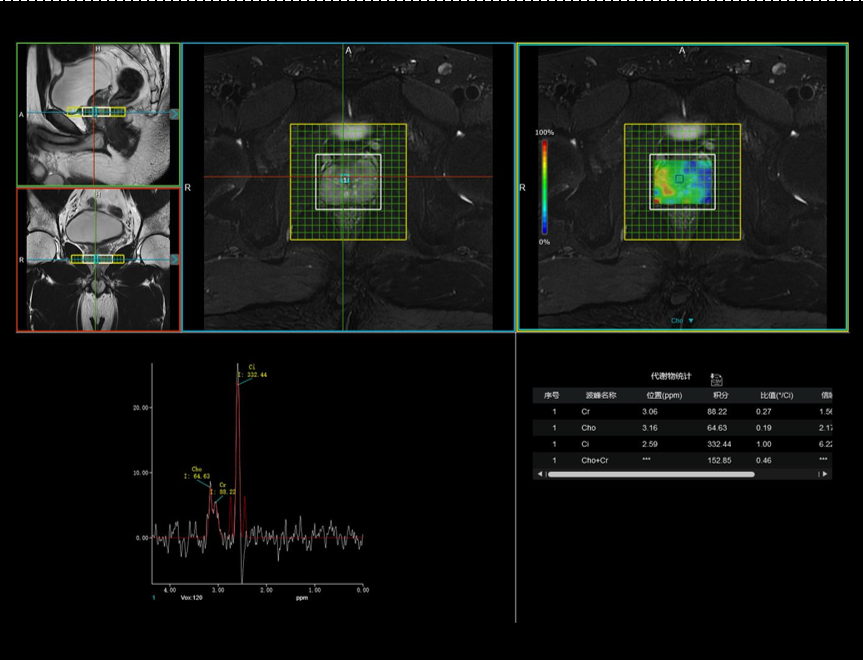

前列腺 MRS